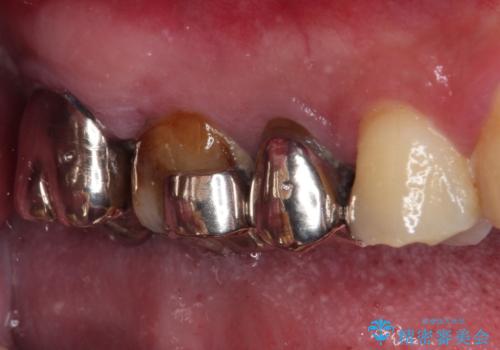

- ものが挟まるとのことで来院された患者様です。

一度は治療せずに放置していましたが、1年後のメインテナンスの際に悪化していることが分かったことから、補綴治療を行うこととしました。

神経を抜いてある歯はむし歯が進行しても痛みを感じることがないため、気がついたときには著しくむし歯が進行している可能性があります。

早めの対応とすることで、抜歯を回避できることはもちろん、外科処置などの本来必要のない処置を行わずに対処することができました。